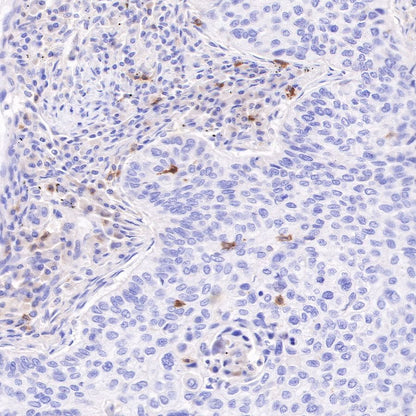

IHC shows positive staining in paraffin-embedded human lung squamous cell carcinoma. Anti-CD103 antibody was used at 1/100 dilution, followed by a HRP Polymer for Mouse & Rabbit IgG (ready to use). Counterstained with hematoxylin. Heat mediated antigen retrieval with Tris/EDTA buffer pH9.0 was performed before commencing with IHC staining protocol.